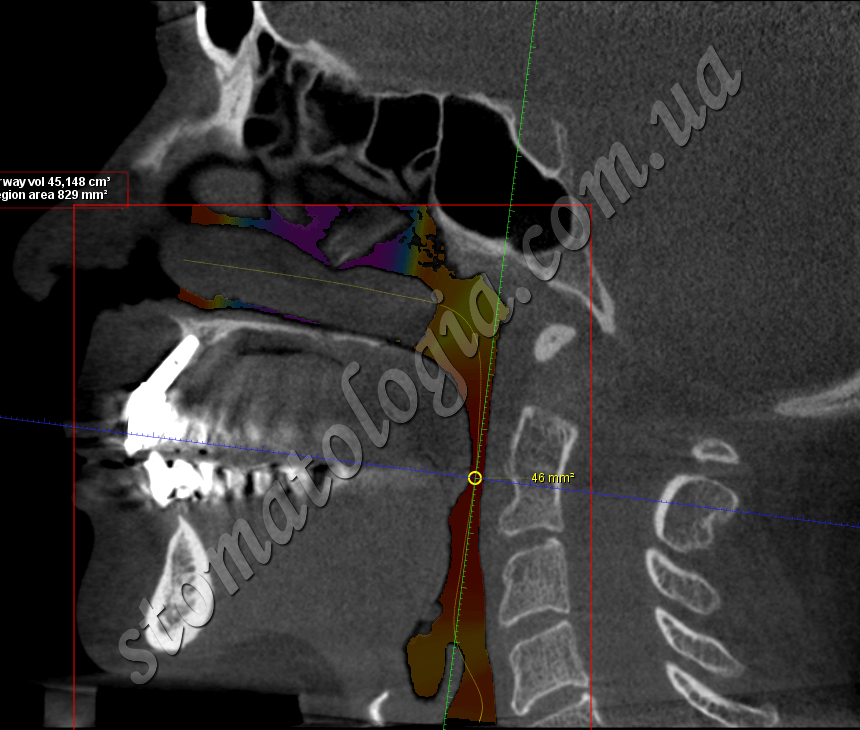

Фото 2-3. Оцінка дихальних шляхів на етапі діагностики

Основне завдання гнатології – з’ясувати, чому змістилася щелепа, визначити її правильне розташування та повернути орган в положення до зміщення. Це прибере скрип і стирання зубів, клацання й біль у суглобі, підклинювання при жуванні чи позіханні. Отже, усі функції зубощелепної системи будуть відновлені. Гнатологія аналізує порушення постави, зіставляє дані ортодонтичної ситуації та функціональність зубощелепної системи. Для грамотного встановлення діагнозу лікар-гнатолог може вдатися до рентген-діагностики або МРТ СНЩС.